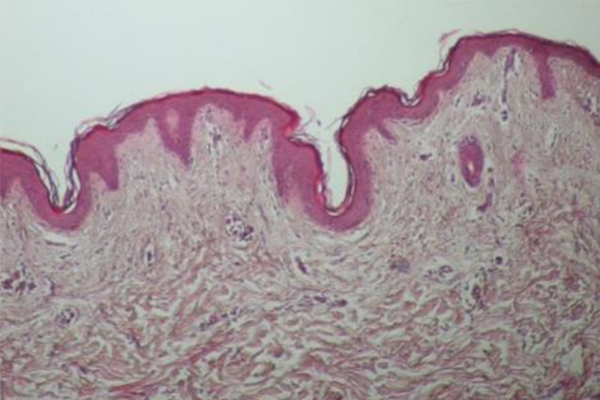

온다 시술전 피부조직